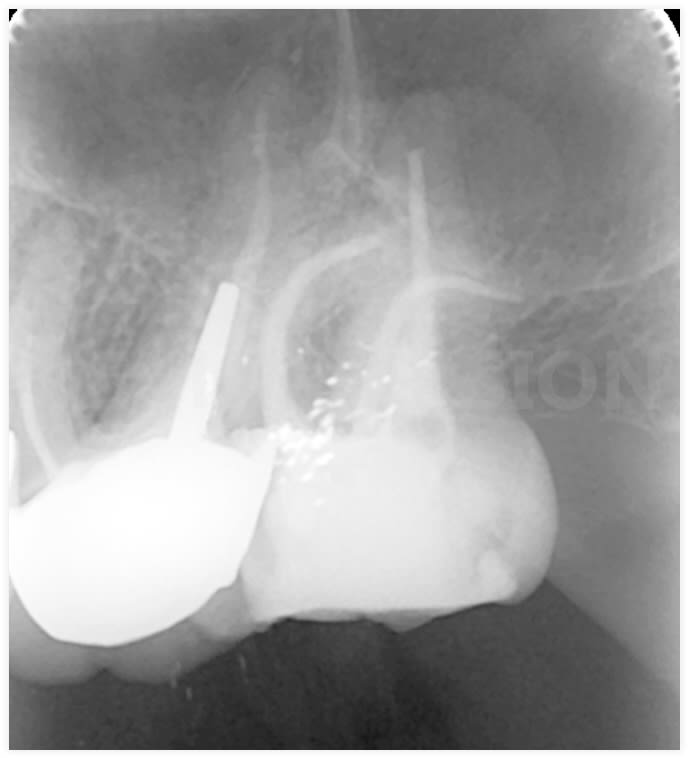

Un grand merci au Reciproc blue!

J'ai pu passer le jaune dans 2 canaux, et le noir dans le DV qui présentait la courbure la plus marquée...

superbe

mais sans vouloir gacher ta joie , il faut en remttre un petit coup en palatin ... ca tombe bien c'est pas le plus compliqué

t'es sur qu'il y a pas une deuxième MV ? ))))))

Je ne pense pas. D'après le localisateur du VDW gold reciproc, je suis bon en palatin (mesure faite juste avant l'obturation).

Pas vu...

Carident, lachmar a repéré un petit manque en palatin, tu sais tres bien que le localisateur d'apex a des plages d'erreur assez importantes, surtout lors d'un petit retrecissement canalaire .

J'ai améilloré le contraste de ta radio pour mieux voir ce palatin. En effet... Ce qui ne veut pas dire forcément qu'on peut faire mieux!

c'est une horreur sur pattes, ta molaire, comme sait bien le faire mere nature pour nous faire suer. bravo.

En fait, je vois bien le dôme apicale radiologique qui est à 2mm de l'extrémité de mon cône de gutta, cela dit, le dome apicale radiologique de correspond pas forcément à l'apex... J'ai tendance à plus croire le localisateur d'apex. Cela dit, je vais avoir un cône beam bientôt, je contrôlerais...